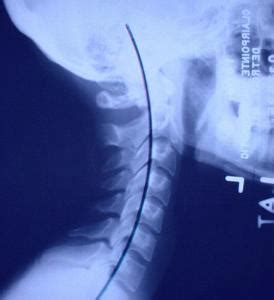

颈椎并不是一条直线,而是有曲度的,但现在很多人在检查的时候,发现颈椎曲度变直,这是怎么回事呢?怎么预防颈椎问题?下面小编就带来介绍。

正常情况下,脊柱不是一条直线,而是一条完美的生理曲线。久坐、长时间玩手机等让当代人的颈椎备受压力,慢慢出现曲度变直。如果放任不管,有可能进展为严重类型的颈椎病。